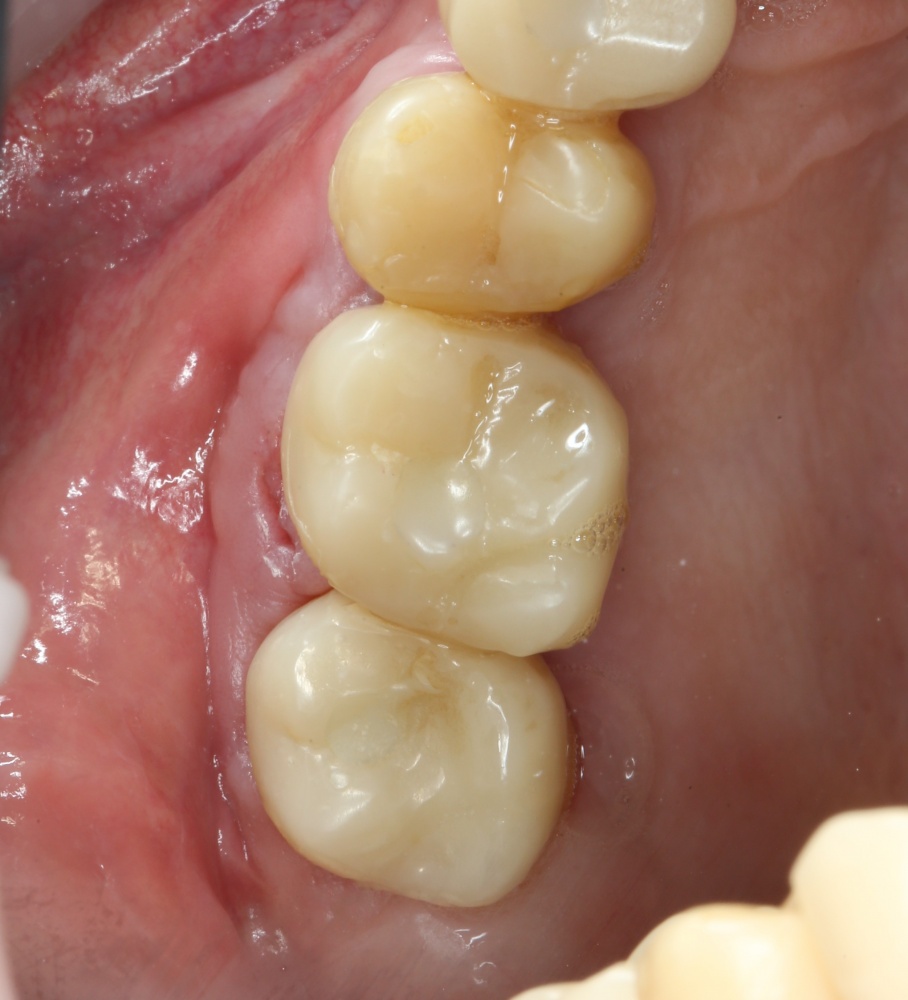

Через пару недель область, где мы провели уже две операции, выглядит примерно так:

или, если снять формирователи:

Можно передавать пациента ортопеду для временного протезирования. Что он и делает: